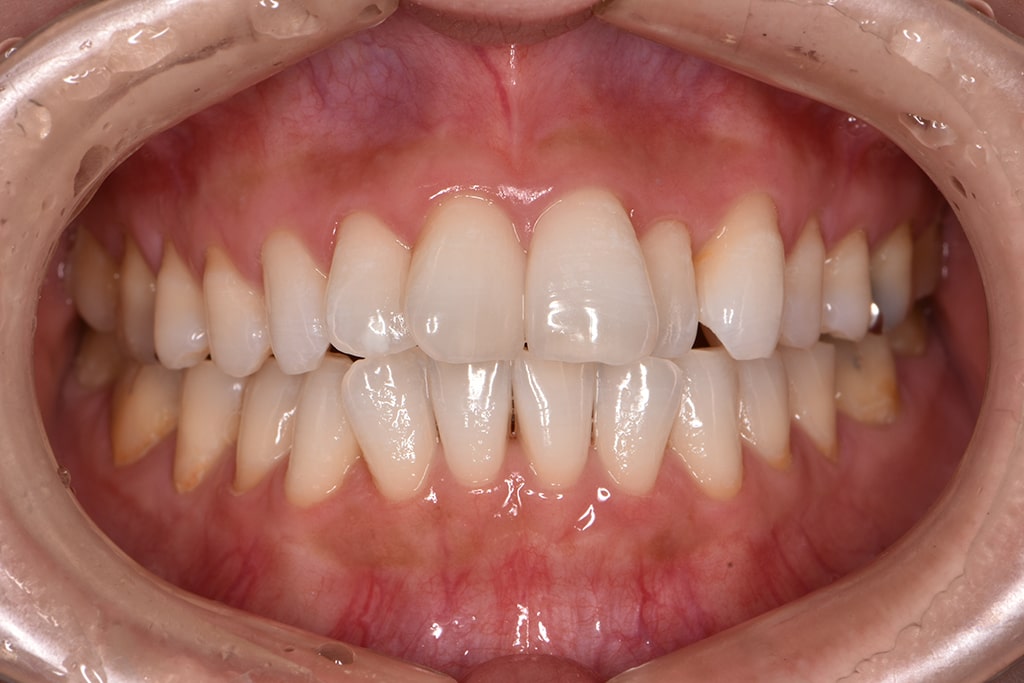

口腔内撮影

現在のお口や歯の状態を確認するために、口腔内の写真を撮影します。